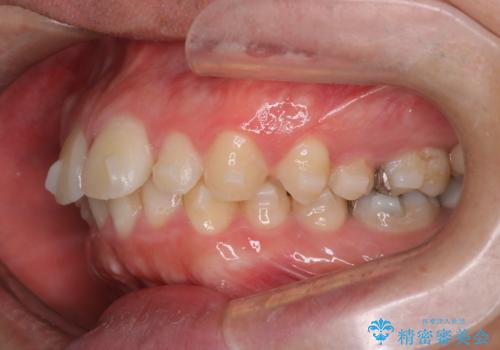

【前突症例】前歯を下げたい

- 前歯の隙間と口元を主訴に来院されました。

インビザラインにて治療を行いきれいな歯並びをつくることができました。

奥歯の噛み合わせもきちんと仕上げることができました。